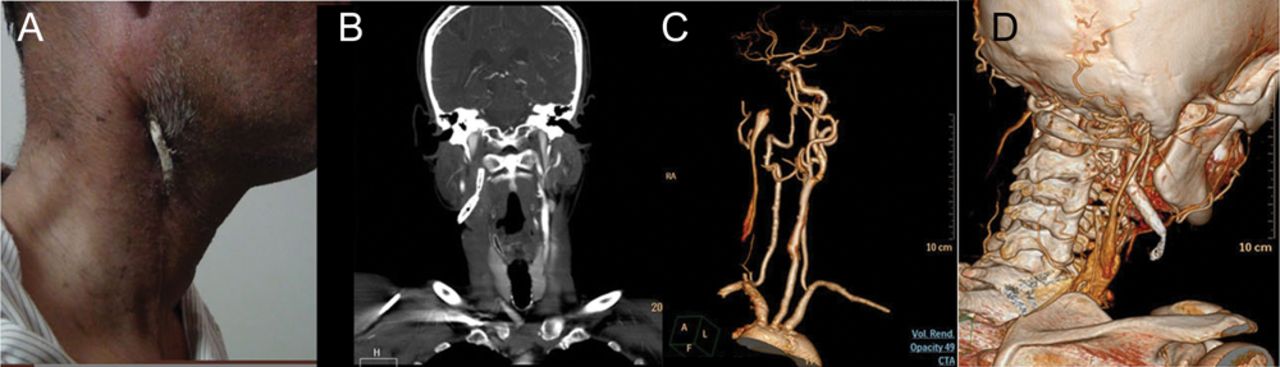

支架是用来治疗postcarotid动脉内膜切除术假动脉瘤的52岁的男人。一年半后,他开发的无症状的挤压支架。CT血管造影显示支架与右颈动脉闭塞(挤压图)。支架移植切除肿瘤。支架挤压是非常罕见的。1支架挤压的原因包括支架低估,持续的假动脉瘤扩张,或颈动脉爆裂时支架部署。

(一)病人的照片显示颈部外支架挤压。最大强度投影(B) CT冠状图像显示流离失所的颈内动脉内支架1结束和其他预测通过颈部软组织表面。(C)体积渲染图像演示了流离失所的支架。(D) CT血管造影术(体绘制技术)显示完整的右颈总动脉闭塞颈内动脉和颈外动脉。也看到的是流离失所的颈内动脉支架1结束。